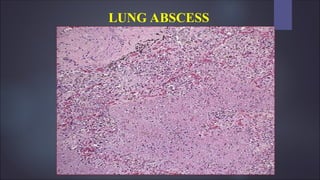

Morphology

 Size – varies from few mm to large cavities of 5 to 6 cm

 Site – may affect any part of the lung and may be single or multiple

 Pulmonary abscess due to aspiration are common on the right side and are

single

 Abscess which develops in the course of pneumonia or bronchiectasis are

usually multiple, basal and diffusely scattered.

 Septic emboli and pyemic abscess – multiple and affect any region of lung

LUNG ABSCESS

 Abscess is suppurative destruction of the lung parenchyma within central

area of cavitation

 Cavity contains suppurative necrotic debris

 Continued infection causes multilocular cavities which are poorly

demarcated

 Chronic cases fibroblastic proliferation in the fibrous wall abscess occurs